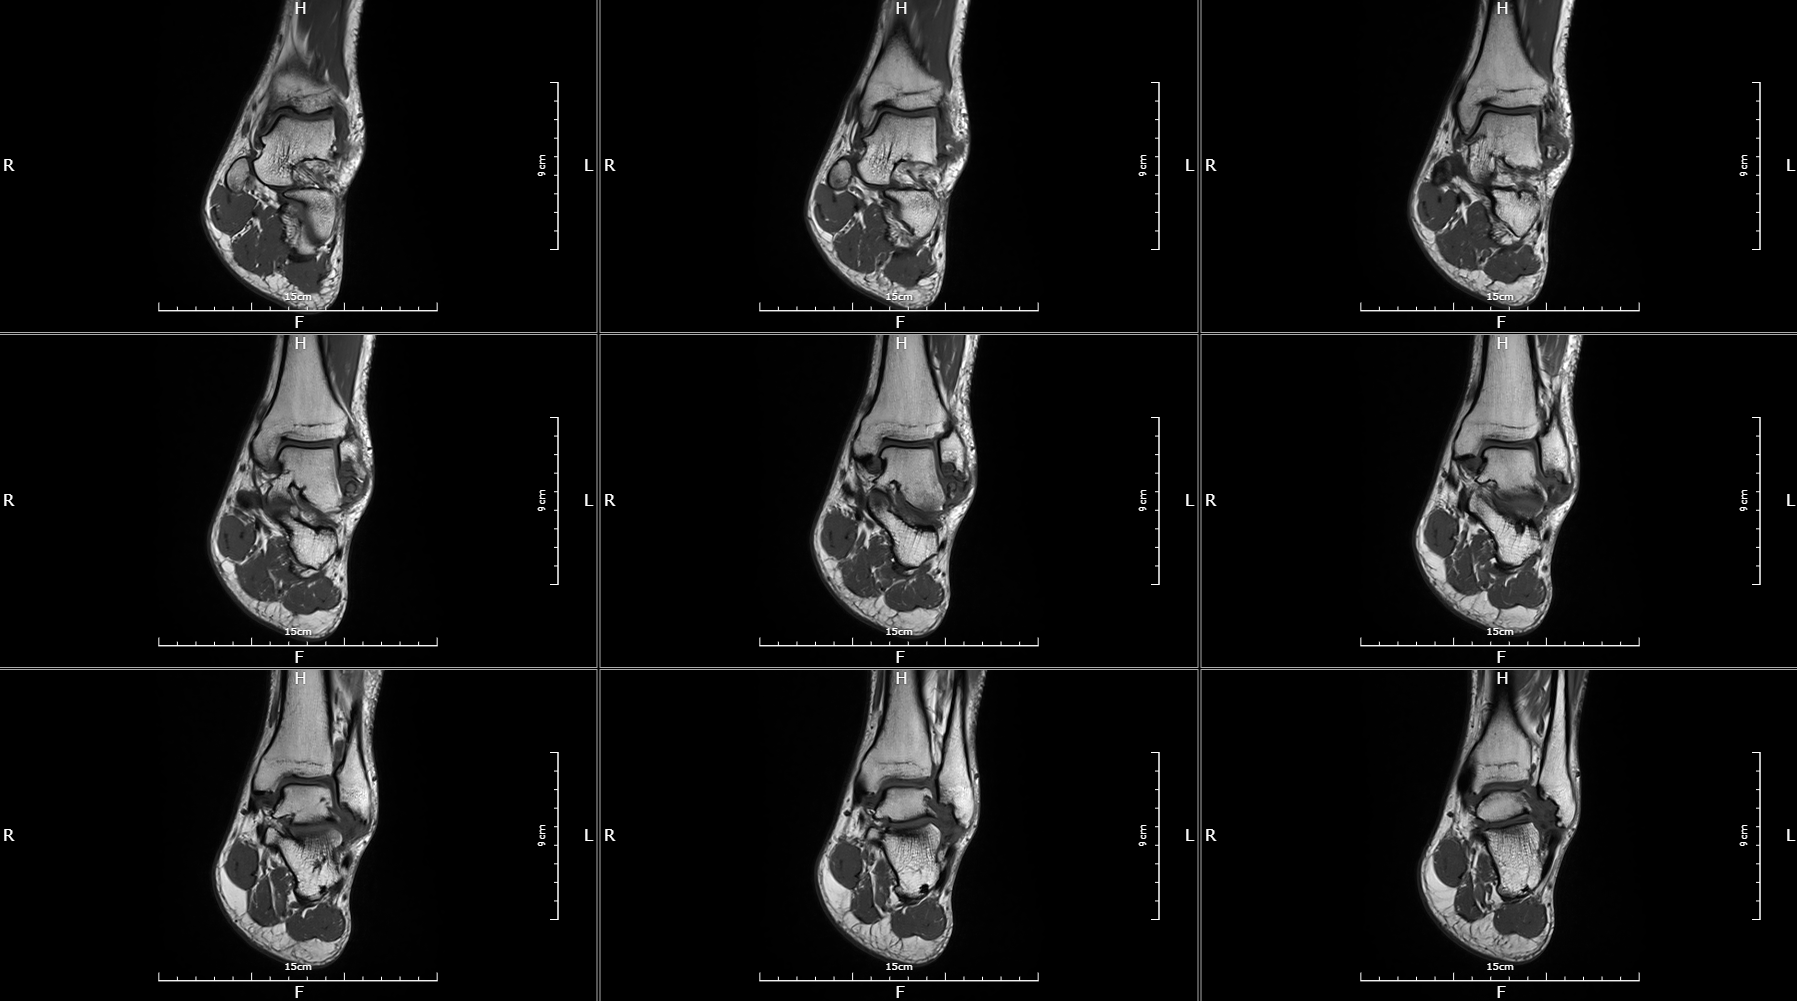

Image gallery